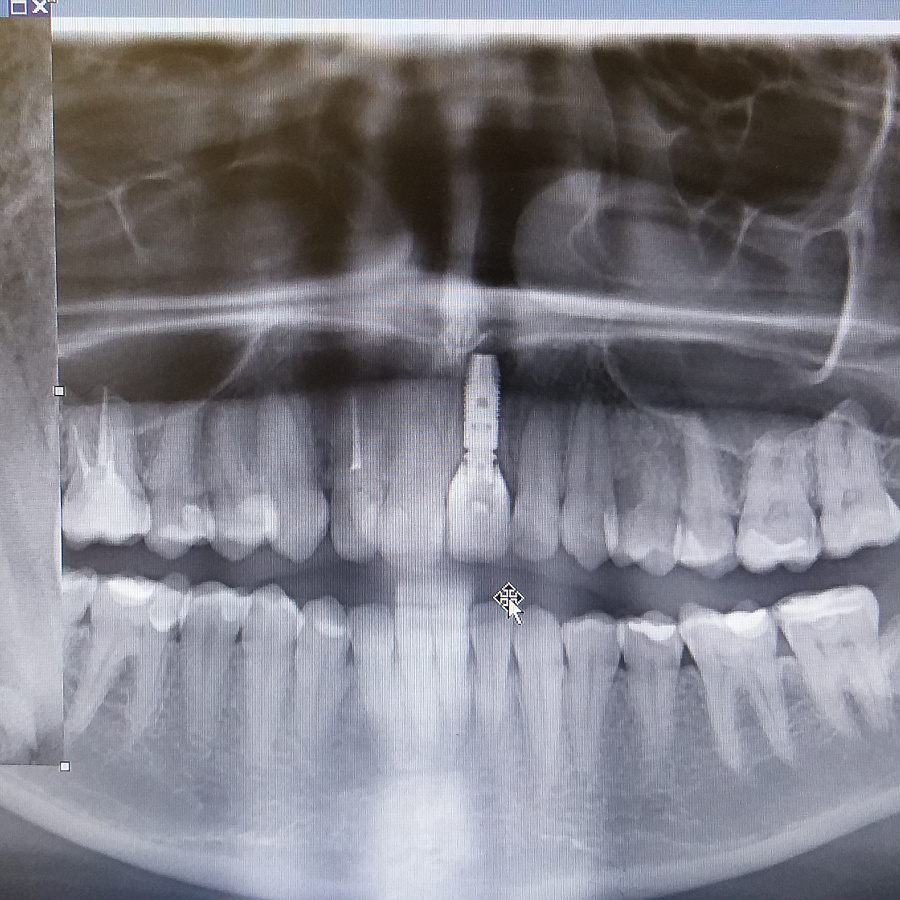

Поставлен диагноз посттравматическая резорбция корня.

Был предложен вариант одномоментной имплантации (удаление зуба и установка импланта за одно посещение).